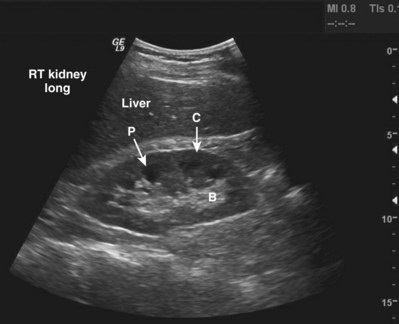

The adult right kidney in the sagittal view demonstrates a cortex that is usually hypoechoic with respect to the liver. The central band of echoes in the kidney is a hyperechoic area that contains the renal hilar adipose tissue, blood vessels, and collecting system. Acoustic shadowing from ribs overlying the inferior pole can be eliminated by moving the probe to a more lateral position or into the intercostal space. By having the patient take a deep breath, the kidney can be moved inferiorly to assist complete imaging (Fig. 4–32).

Figure 4–32 Midsagittal plane of the kidney. Note the relative hypoechogenicity of the renal pyramids (P) compared with the cortex (C). The central band of echoes (B) is hyperechoic compared with the cortex. The midsagittal plane will have the greatest length measurement pole to pole. A perfectly sagittal plane will result in a horizontal long axis of the kidney.